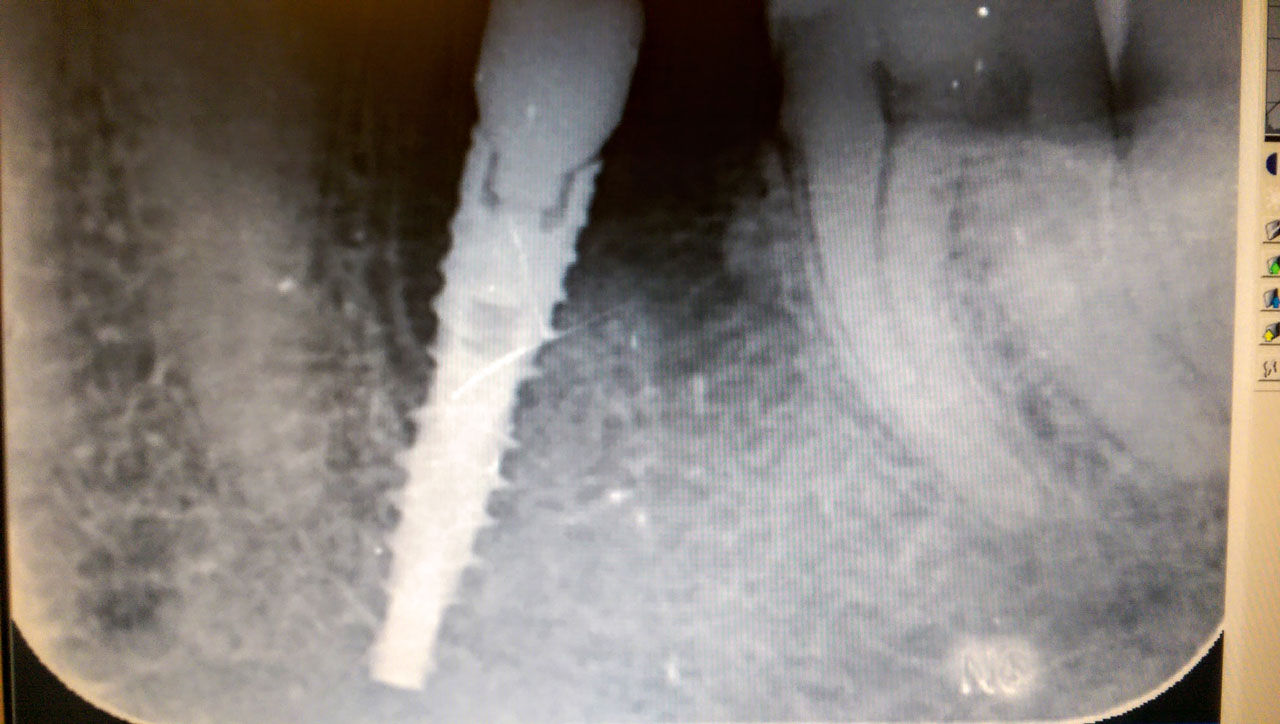

Neki köszönhetően, a világon már több mint 100 000 ember életminősége javult azáltal, hogy ezt a nagyszerű fogpótlási eljárást választotta. Az azonnal terhelhető implantátum kifejezetten gyorsan, 72 óra alatt rögzíthető és persze a kis csapvégekre rákerülnek az ideiglenes fogak is, amelyeket tulajdonosuk rögtön ki is próbálhat.